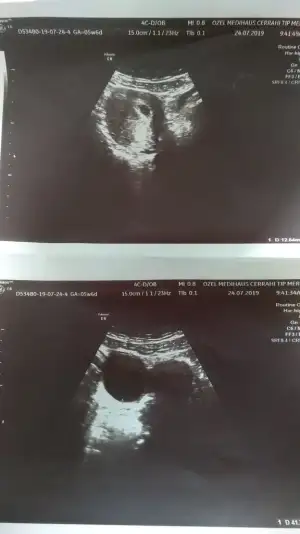

Kızlar doktordan geliyorum şükür ki sıkıntı yok tam 5+6 günlük.2hafta sonra kalp atışı icin cagirdi..Kanın çok iyi dedi.Sadece folik asit aliyorum.

O gece ki şiddetli karin kasik ağrım masummuş yani☺️

Buda kendileri ❣️😊

Eklentiler

• IMG_20190724_110724.webp

IMG_20190724_110724.webp

21,5 KB · Görüntüleme: 86